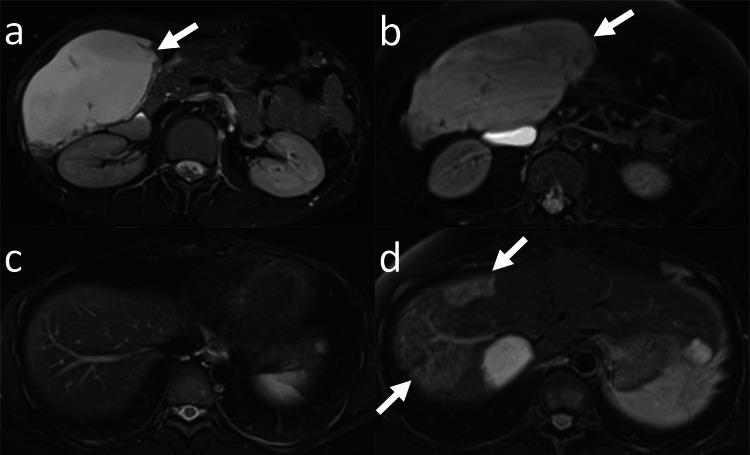

Computed tomography (CT) and magnetic resonance imaging (MRI) reports at Kyoto University Hospital, Kyoto, Japan, between January 2001 and March 2023 were retrospectively searched to find adult patients with hepatic hemangiomas >10 cm. Patients who were followed up without treatment for over six months were included. The maximum diameter of the hepatic hemangioma was compared between the baseline and the final CT or MRI. The clinical course of the patients was evaluated.

Twenty-two patients (17 women, five men; median age, 51 years) were identified. The median diameter of hepatic hemangiomas in the baseline study was 114 mm. Two patients had abdominal distention at the time of the baseline imaging, whereas the others were asymptomatic. After follow-up without treatment (the median; 95.5 months), enlargement, no change, shrinkage of hepatic hemangioma was observed in six, 11, and five patients, respectively. The median growth rate of hepatic hemangiomas was 2.5 mm/year. Two patients underwent liver resection for hepatic hemangioma, while the others were followed up without treatment. In four patients, symptoms appeared or worsened. Two patients died: one patient died from prostate cancer progression; the cause of death for the other was not confirmed.